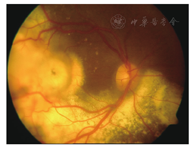

患者女性,8岁。因右眼视力下降1周于2009年1月22日就诊于遵义医学院眼科门诊。全身检查未见异常,自发病以来无眼部红肿、疼痛症状,无外伤史、中枢神经系统及全身疾病史。眼科检查:视力:右眼CF/40 cm,左眼0.8。裂隙灯显微镜检查眼前节未见明显异常。散瞳后眼底镜检查可见血管异常扩张,视网膜下方、黄斑区及颞侧见黄白色渗出,脂质沉着,病灶周围小血管扩张(图1)。荧光素眼底血管造影(FFA)显示右眼病灶内及周围视网膜毛细血管扩张,管壁荧光渗漏,微血管瘤,颞侧、颞下方网膜大片无灌注区,后期荧光增强(图2)。右眼OCT显示黄斑区网膜隆起,明显增厚,网膜下见不规则反射光带(图3)。诊断为右眼视网膜毛细血管扩张症。先后两次予右眼视网膜光凝治疗,治疗后7个月复查右眼视力为0.02。2012年患者因视力再次下降2月,到北京市第三人民医院就诊,B超显示右眼玻璃体混浊,下方及颞侧眼球壁钙化,其后可见声影,可见视网膜脱离(图4)。诊断为右眼视网膜毛细血管扩张症,未予特殊处理,建议观察。2014年患者再次到我院复诊,右眼视力CF/40 cm。右眼B超提示玻璃体混浊,可见眼球壁钙化(图5)。眼眶CT检查见右眼球轻度萎缩,右眼球两侧壁、后壁高密度影(图6)。诊断:右眼毛细血管扩张症晚期转化为眼球痨。

本例患者有典型的视网膜毛细血管扩张症的眼底表现,且眼底彩照及FFA也支持其诊断,CT及B超可见球后壁钙化,CT可见右眼球萎缩,因此我们考虑诊断为视网膜毛细血管扩张症晚期转化为眼球痨。孙为荣等[5]通过对诊断为视网膜毛细血管扩张症病理结果的观察发现视网膜毛细血管扩张症晚期可出现钙化及骨化。其主要原因可能为:(1视网膜毛细血管扩张症常见视网膜血管畸形扩张,这种血管畸形有时是以微血管瘤出现的,有血管瘤就会有钙化(本例患者初诊时FFA显示病变周围大量微血管瘤)。(2)视网膜毛细血管扩张症是一种缓慢反复的过程,可有新老病变交替,病情时重时轻,以后形成瘢痕组织成为增殖性视网膜炎,有瘢痕组织就有钙化的可能。病程长可能也增加了钙化的机会。本例病人初诊时视网膜下未见钙化,5年后随诊是眼底已窥不见,CT检查显示眼球两侧壁、后壁出现与眶骨一致的高密度影,提示合并钙化。毛细血管扩张症晚期转化为眼球痨需与脉络膜骨瘤相鉴别,后者常不伴其他眼部病变。目前该病例尚缺乏毛细血管扩张症晚期是否合并脉络膜钙化或脉络膜骨瘤的证据,毛细血管扩张症晚期是否会向脉络膜骨瘤转化,且二者之间是否存在某种关系,国内外均无资料报道,值得进一步探讨。